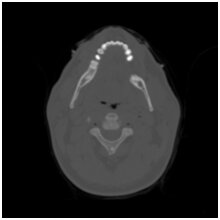

Many segmentation techniques exist in the literature. Well known is global thresholding with automated threshold selection based on the image histogram, e.g. Otsu's method. Other commonly used methods are region growing, watershed segmentation, active contours, etc. In the setting of CT, these techniques base themselves exclusively on the tomographic reconstruction or the tomogram. In practice, however, these tomograms will not be completely accurate because of reconstruction error and artefacts (e.g. due to noisy or insufficient data) and the useof classic segmentation techniques will thus also lead to inaccurate segmentations. Therefore, we develop objective segmentation methods that not only use the tomogram, but also the available projection data.

One such technique is the Projection Distance Minimization method (PDM). For a given threshold (either global or local), partitions are defined. Then, for each partition the grey level is estimated in a way such that the projection distance will be minimal. A forward projection of this segmentation will be created and its euclidean distance to the real projection data will be measured. The optimal segmentation is the one such that this distance is minimal. Experiments have shown that this method indeed creates superior segmentations when compared to classic techniques such as Otsu's. The difference is mostly noticeable when the amount of projection angles is small. This means that high accuracy segmentations can be made while limiting the dose used in the tomographic process. This is very important in biomedical studies on rats or mice.

Another technique is the Segmentation Consistency Maximization method (SCM). Most segmentation techniques assume that the number of different partitions in the image domain is limited. This is not always the case and often one is interested in finding the object with the highest, homogeneous density (e.g. a metallic implant) amidsts objects of a varying densities (e.g. bones and tissue). The SCM-algorithm finds a global threshold to distinguish between the metallic object and the background by minimizing the A-incosistency of the residual sinogram. The latter is the projection data minus the forward projection of the segmentated dense object. The concept of A-inconsistency means the amount of inconsistency of a sinogram given the fact that a number of pixels (those belonging to the dense object) may not be used in a reconstruction. This value is measured by creating an iterative reconstruction of the residual sinogram and comparing its forward projection to the residual sinogram.